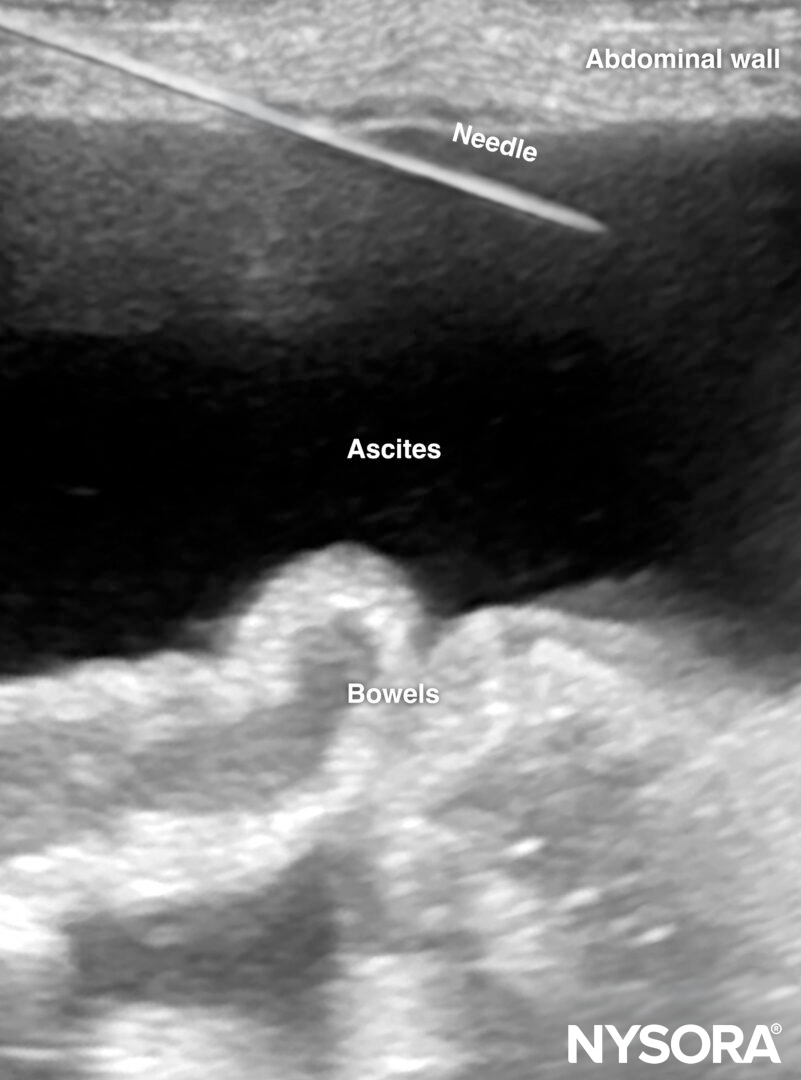

- Insert the needle in-plane from a lateral to medial direction.

In-plane insertion of a needle during paracentesis in the LLQ.

- Keep in mind that the visceral structures (bowels) move autonomously, contain air, and therefore tend to float up. Therefore, during needle insertion, monitor floating structures to reduce the risk of bowel puncture and needle contamination.